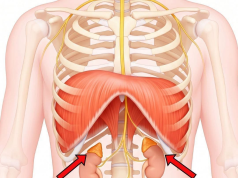

– Cơ hoành (Diaphragma): Ảnh hưởng nhịp tim khi thở

– Thận nằm sau phúc mạc, được bao quanh bởi Gerota fascia

– Mạc cơ tương liên: Fascia của Cơ thắt lưng – chậu (Psoas – Iliacus)

– Thoracolumbar fascia (mạc ngực – thắt lưng): nối Thận – Cột sống – Cơ dựng sống – Cơ chéo bụng)

(Hình ảnh đính kèm: )